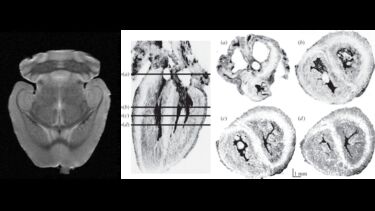

The scanner is routinely used in mouse and rat brain imaging at high resolution, typically voxel resolution is 100 μm but can be smaller if required. Images can be enhanced with gadolinium contrast agents, for example to highlight tissue lesions.